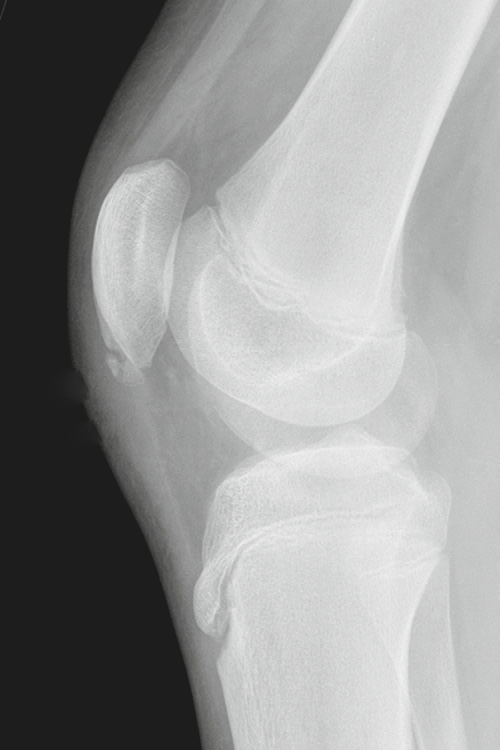

Osgood-Schlatter lesion

aka Tibial tuberosity avulsion

Chronic avulsive injury of the patellar tendon at its inferior attachment

Findings:

• bony fragmentation of the tibial tubercle/tuberosity

• thickening and indistinctness of distal patellar tendon

• associated soft tissue swelling

How well did you know this?